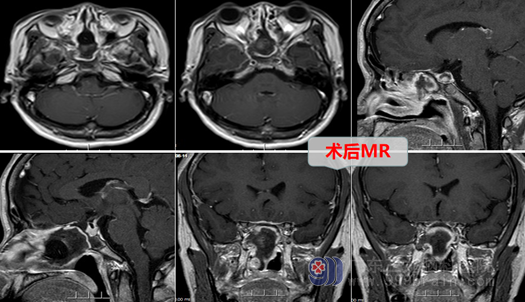

欧阳辉教授带领外十科团队进行了认真的术前讨论,医生耐心详细地与何女士及其家属进行解释、谈话,终于解除了何女士心中的恐惧,她和丈夫都同意按医生的方案进行治疗。外十科团队在完善术前准备后,为何女士择期进行了内镜下经鼻蝶入路鞍上区Rather s囊肿切开引流术及大部分囊壁切除术。原来连打针都害怕的何女士在医生、护士鼓励下,硬着头皮进了手术室,医生耐心地安慰她,麻醉后,很快微创手术就做完了。手术很顺利,何女士得到了满意的治疗,术后回到病房,丈夫看见她头部连伤口没有,也没有纱布和绷带,更是非常高兴。现在她正一天天好转,很快就要恢复出院了。何女士感慨地说:微创手术真是太好了,人得了脑瘤,如果手术顺利,那么有一种感触:就是劫后重生,真要特别感谢外十科医生护士。